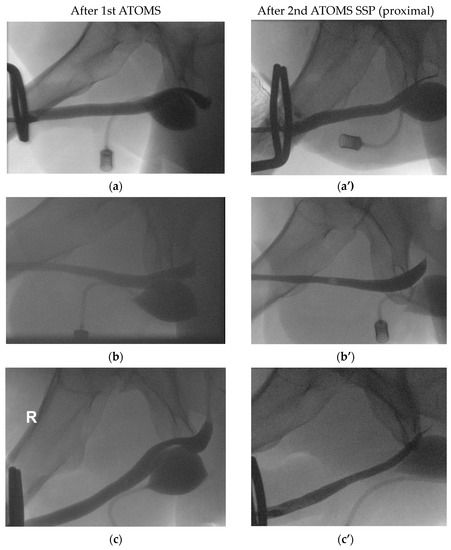

| 1st ATOMS SSP | ||||

| 2nd ATOMS SSP (proximal) | ||||